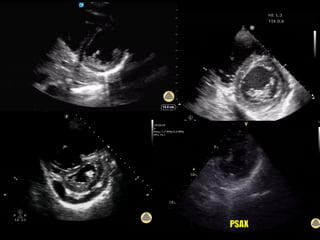

PARAESTERNAL EIXO CURTO

Paraesternal eixo curto mostrando os territórios irrigados pelas três principais artérias

coronárias: Descendente Anterior (DA), Circunflexa (Cx) e Coronária Direita (CD).